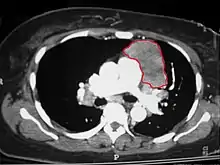

| An encapsulated thymoma (mixed lymphocytic and epithelial type) | |

When a thymoma is suspected, a CT/CAT scan is generally performed to estimate the size and extent of the tumor, and the lesion is sampled with a CT-guided needle biopsy. Increased vascular enhancement on CT scans can be indicative of malignancy, as can be pleural deposits.[1] Limited biopsies are associated with a very small risk of pneumomediastinum or mediastinitis and an even-lower risk of damaging the heart or large blood vessels. Sometimes thymoma metastasize for instance to the abdomen.[5]